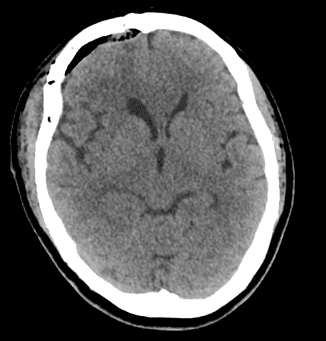

Ca phẫu thuật diễn ra thuận lợi. Sau mổ 4 giờ, bệnh nhân tỉnh táo, cử động tứ chi bình thường, hình ảnh CT kiểm tra cho thấy khối u đã được lấy hết hoàn toàn. Bệnh nhân hồi phục tốt và được xuất viện sau 5 ngày điều trị.

Hình ảnh MRI trước mổ (trái), CT sau mổ (giữa), khối u (phải)